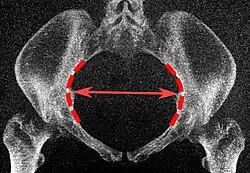

The diameters or conjugates of the pelvis are measured at the pelvic inlet and outlet and as oblique diameters.

| Name | Description | Average measurement in female |

|---|---|---|

| Anteroposterior or conjugate diameter or conjugata vera | Extends from the upper margin of the pubic symphysis to the sacrococcygeal joint; | about 110 mm. |

| Transverse diameter | Extends across the greatest width of the superior aperture, from the middle of the brim on one side to the same point on the opposite; | about 135 mm. |

| Oblique diameter | Extends from the iliopectineal eminence of one side to the sacroiliac articulation of the opposite side; | about 125 mm. |

| Anatomical conjugate | Extends from the pubic symphysis to the promontory; | about 120 mm. |

| Diagonal conjugate | Extends from lower margin of the pubic symphysis to the sacral promontory; | about 130 mm. |

| Straight conjugate | Extends from the lower border of the pubic symphysis to the tip of coccyx. The coccyx can bend posteriorly and expand the diameter with 25 mm; | about 95 mm (+ 25 mm). |

| Median conjugate | Extends from the lower border of the pubic symphysis to the lower border of the sacrum; | about 115 mm. |

Low-dose CT scan of the transverse diameter of the pelvic inlet, as part of pelvimetry -